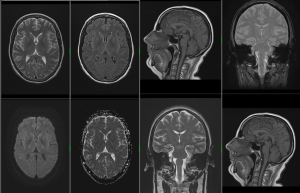

MR mozku

Nádorová onemocnění, zánětlivá onemocnění – zvláště pak demyelinizační onemocnění bílé hmoty (roztroušená skleróza), epilepsie, cévní onemocnění (malformace, aneuryzmata), neurodegenerativní onemocnění, vrozené vady, hydrocephalus všech typů, bolesti hlavy, psychické změny (včetně psychotických onemocnění), onemocnění hypofýzy a mozkových nervů, následky úrazů hlavy (zvláště se zaměřením na difusní axonální poranění a rozpadové produkty hemoglobinu (ferritin a hemosiderin)), MR je možno provést u akutních krvácení a k posouzení fraktur lebky, ale zde je vhodnější provedení CT.

Na našem pracovišti provádíme vyšetření mozku, orbit, hypofýzy, krční páteře, hrudní páteře, bederní páteře, kolenního kloubu, ramenního kloubu, jater a pankreatu, MRCP, ledvin a nadledvin, pánve, MR enterografii, MR angiografii intrakraniálních tepen, MR angiografii mozku – venózní, MR angiografii karotid, MR angiografii tepen dolních končetin, MR angiografii renálních tepen a vyšetření ostatních kloubů těla.